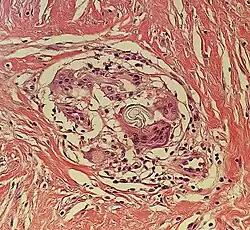

| Kaposi’s sarcoma in patch stage | The patch stage typically shows irregular proliferation of jagged vascular channels in the dermis below an integral epidermis. The so-called promontory sign is sometimes found in patch stage lesions and denotes vascular spaces surrounding pre-existing blood (see image).[23]

vessels |

|